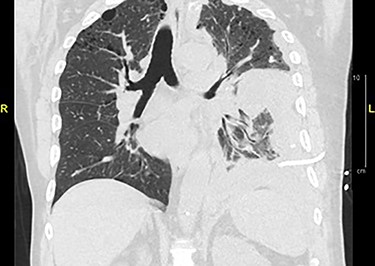

Chemotherapy was refused by the patient postoperatively. After 6 weeks, the patient returned to the emergency room presenting with shortness of breath, due to left-sided pleural effusion requiring thoracentesis. Cytology was negative for malignancy. He returned 3 weeks later with similar respiratory symptoms. A CT chest showed recurrent left pleural effusion (Fig. 4). Thoracic surgery was consulted and a pleural biopsy with PleurX catheter insertion was performed. Metastatic, dedifferentiated liposarcoma was reported. During his hospital course, the patient developed worsening respiratory failure and died after he was treated with broad-spectrum antibiotics for pneumonia and suspicious COVID-19, which was later reported positive.

CT chest without contrast: extensive lobulated left-sided pleural thickening with effusion, consistent with metastatic disease.